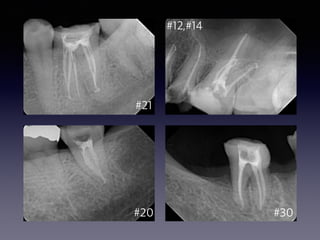

Endodontic sealer

#30

#9, #10

#12,#14

#21

#20 #30

2014 11 102014 11 18 2014 11 19 2015 02 26